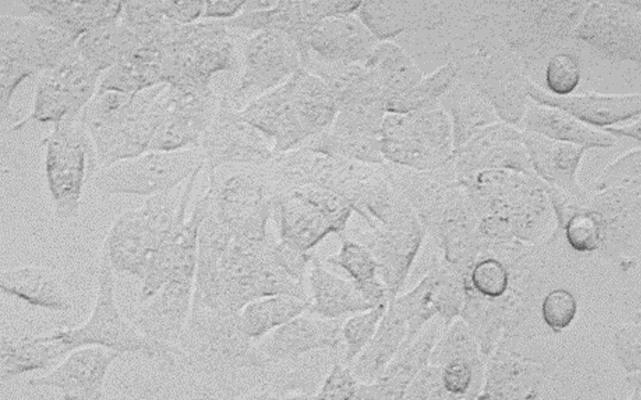

BEL-7402;人肝癌细胞

LTEP-α-2;人肺腺癌细胞

RPMI-8226;人多发性骨髓瘤细胞

SK-N-DZ;人成神经瘤细胞-骨髓

MHCC97-H;高转移人肝癌细胞

HCCLM3;高转移人肝癌细胞

K562;人慢性髓系白血病细胞

C3A;人永生化肝细胞

Changliver;人张氏肝细胞